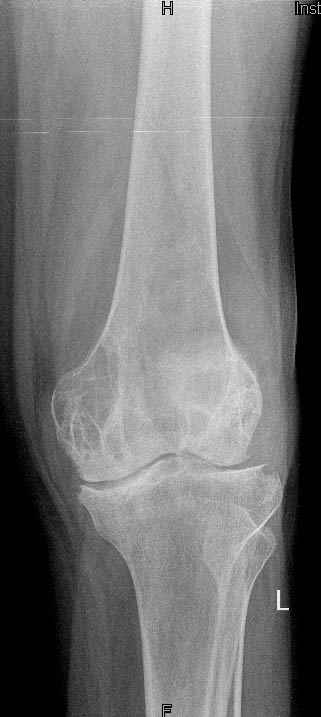

Коллеги!Окажите, пожалуйста, консультативную помощь.Мужчина, 41 год, 15 лет состоит на учете по поводу ревматоидного полиартрита, гормонзависимый (преднизолон получает нерегулярно). В процесс вовлечены крупные и мелкие суставы. 01.01.06 - без травмы наступил патологический перелом на границе н/3-с/3 бедра (перелом на фоне кистозных изменений?) Биопсия из зоны перелома - <реактивные изменения в очаге перелома>, без признаков опухоли. На рентгенограммах, помимо перелома, кистозные изменения на мыщелках б/берцовой кости и мыщелке бедра с другой стороны. До травмы со стороный коленных суставов был болевой синдром, функция практически в полном объеме. Какие будут предложения по тактика лечения перелома и кист на противоположом бедре? Заранее благодарю! С уважением, А.В.Владзимирский Донецкий НИИ травматологии и ортопедии Донецк, Украина

I would do a proper reserch into those cysts looking for a reason of teir appearance-osteitis

fibrosa cystica or others,

There are rules for preventive nailing-if the pathology occupies more than 1/2 of the

diaphysis-otherwise it should be left alone.